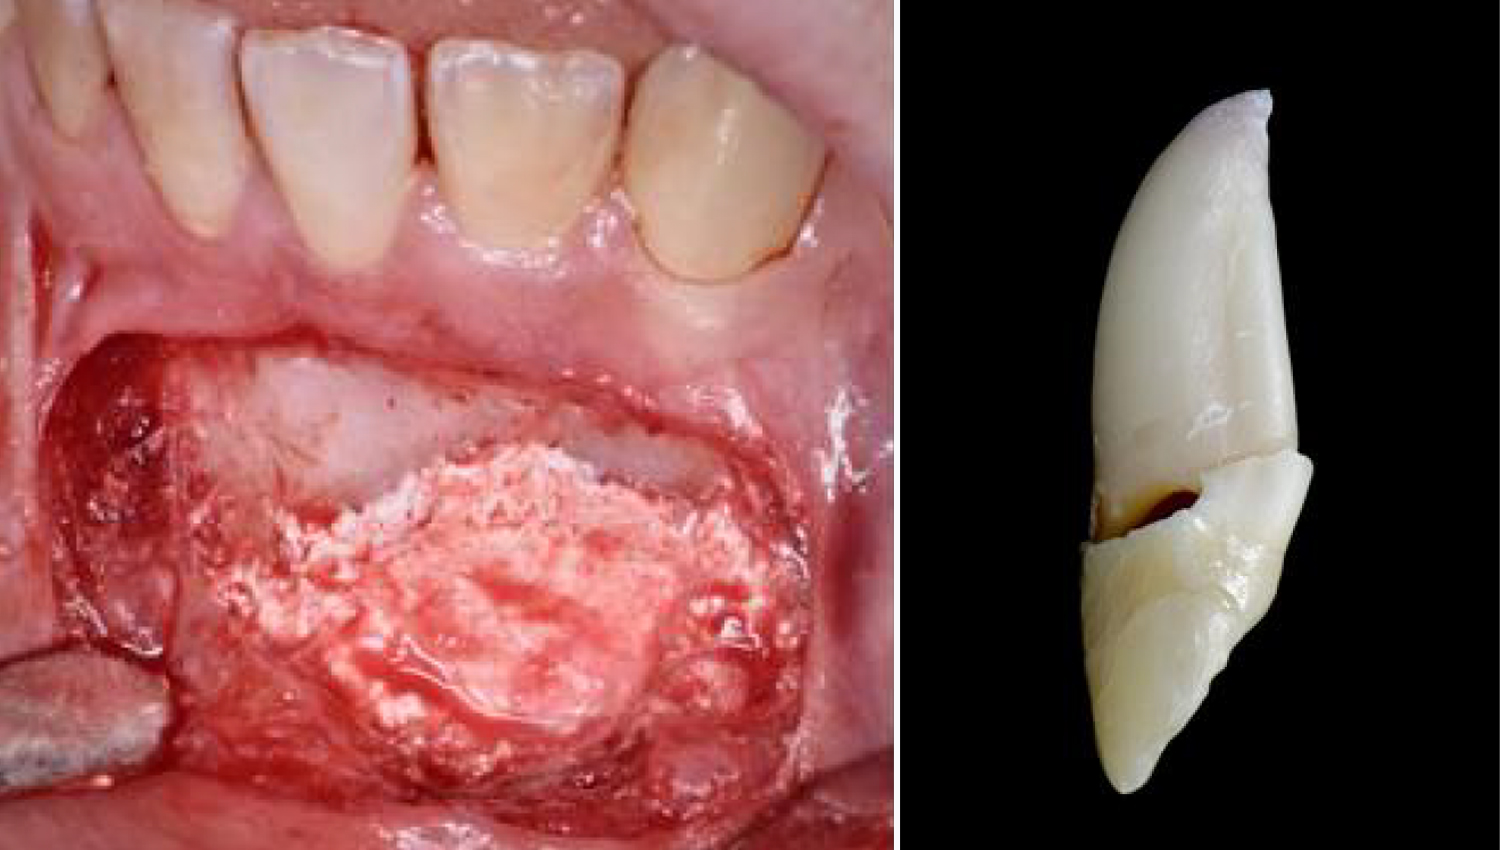

4.4. The Bone defect filled with Powerbone Dental Putty. No barrier membranes were used (left picture). The sectioned impacted tooth after removal (right picture).

5.Two months post-op, clinical view showing excellent healing of the area. The patient is now ready to start the orthodontic treatment on the lower arch.